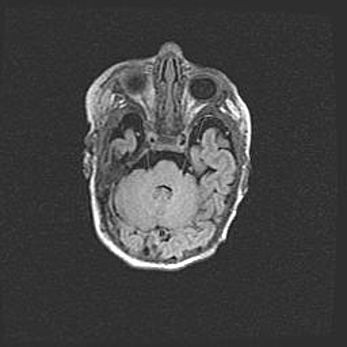

Аномалия Денди-Уокера. Признаки гипоплазии мозолистого тела.

Возраст: 5 месяцев 3 дня

Вес: 5550 г

Пол: мужской

Окружность головы: 39 см

Срок гестации: 40 недель

Аномалия Денди-Уокера – это порок развития головного мозга, для которого характерна триада симптомов: гипотрофия или аплазия червя мозжечка и/или полушарий мозжечка, расширение четвёртого желудочка с формированием ликворной кисты задней черепной ямки, гипертензионная гидроцефалия различной степени.

Гипоплазия мозолистого тела относится к дефектам внутриутробного этапа развития мозговой ткани, возникающим в процессе закладки структур головного мозга, что происходит на начальных этапах развития эмбриона.